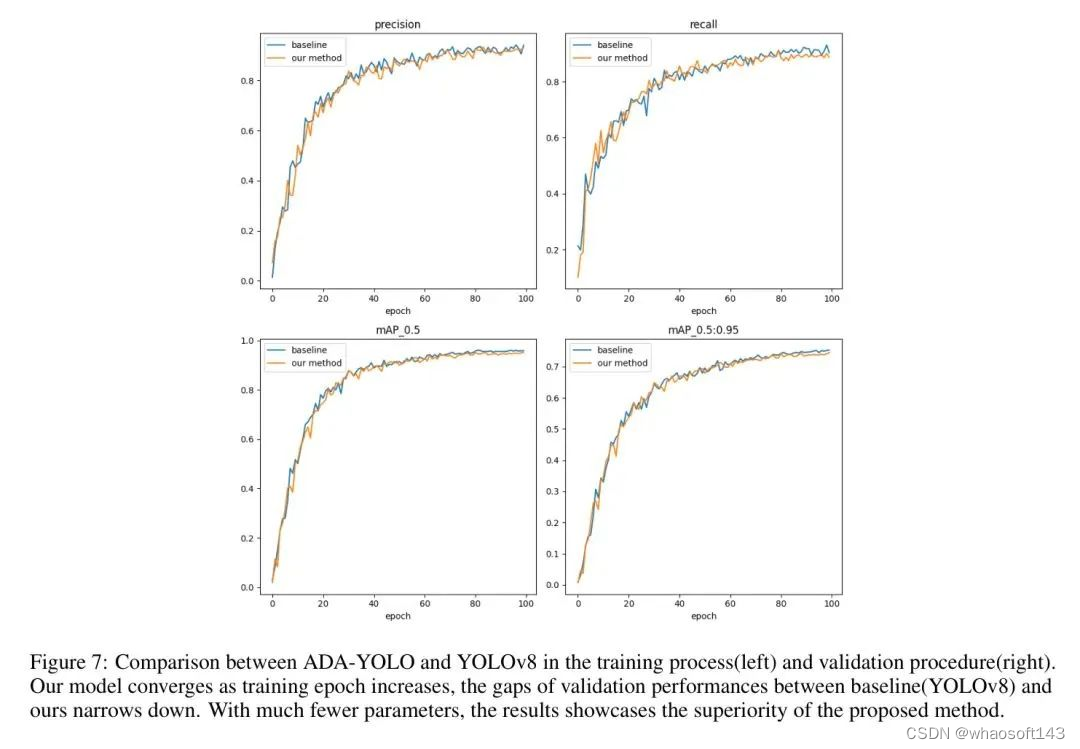

值得注意的是,该实验只包含一组超参数,在模型微调后,作者认为其性能可以更好,最终可以大大超过 Naive 方法,如图 7(a) 所示。如第 2.2.3 节所述,总体损失分为三个组成部分:边界框损失、分布对焦损失和分类损失。从图中可以看出,随着训练周期增加,模型损失和作者的模型(橙色线)损失都持续减小并收敛到某个位置,而作者的模型(橙色线)所需的参数较少,内存使用较少。这种现象强烈地表明了新颖架构的积极影响。

在本文中,作者提出了一个内存高效的 ADA-YOLO 模型,该模型利用新颖的架构和训练策略来增强医学图像中多目标检测的鲁棒性。通过在各种数据集上的实验,证明了 ADA-YOLO 在处理医学图像中的遮挡相关挑战方面具有优越性能。模型在准确局部化和分类多个目标方面,即使在遮挡条件下也表现出卓越性能,因此,由于其创新的 Adaptive Head 设计,它在计算机辅助诊断检测方面具有广阔的未来。

然而,这项工作也有一些局限性:首先,大数据集仍然需要消耗大量的训练和推理时间,这可能取决于实际环境中的硬件;其次,模型可解释性可能是一个潜在的副作用。通过智能利用深度机制和领域知识,如多模型嵌入,模型可以变得更加可靠和可解释,为作者的未来工作铺平道路。

在本文中,作者提出了一种内存高效的 ADA-YOLO 模型,该模型利用新颖的架构和训练策略来增强医学图像中多目标检测的鲁棒性。通过在各种数据集上的实验,证明了 ADA-YOLO 在处理医学图像中的遮挡相关挑战方面具有优越性能。模型在准确局部化和分类多个目标方面,即使在遮挡条件下也表现出卓越性能,因此,由于其创新的 Adaptive Head 设计,它在计算机辅助诊断检测方面具有广阔的未来。

然而,这项工作也有一些局限性:首先,大数据集仍然需要消耗大量的训练和推理时间,这可能取决于实际环境中的硬件;其次,模型可解释性可能是一个潜在的副作用。通过智能利用深度机制和领域知识,如多模型嵌入,模型可以变得更加可靠和可解释,为作者的未来工作铺平道路。